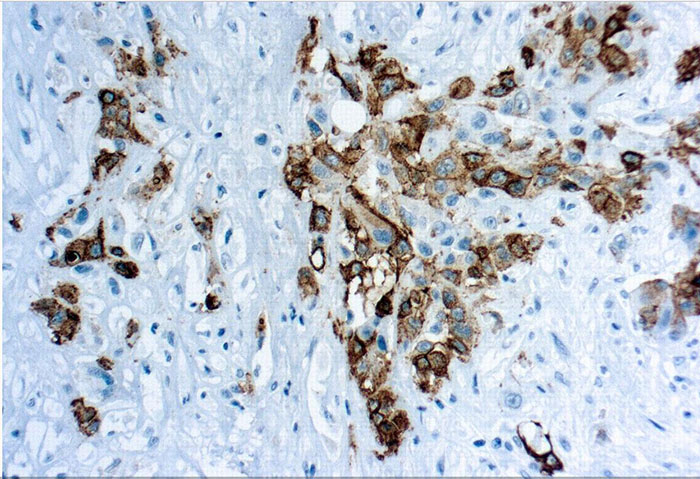

Mesothelin is a glycocylphosphotidylianositol-linked cell-surface glycoprotein, which is present on the surface of normal mesothelium and is overexpressed in many patients with epithelial ovarian cancer and malignant mesotheliomas.

Clone YP158